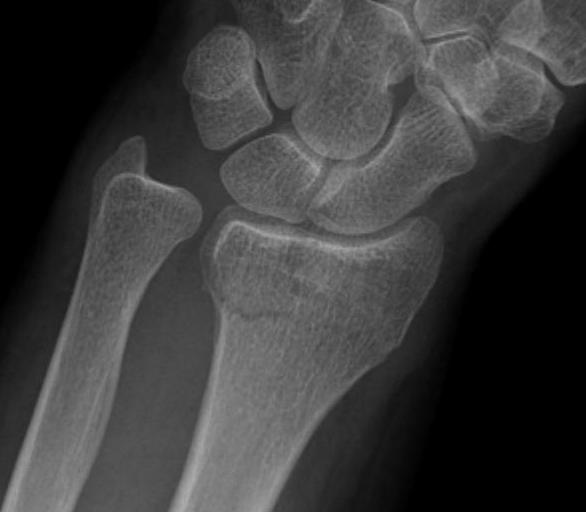

Dr shortDR short

Distal radius fracture with shortening and dorsal tilt